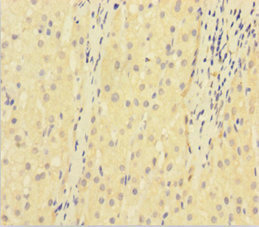

Immunohistochemistry of paraffin-embedded human liver cancer using CSB-PA07279A0Rb at dilution of 1:100